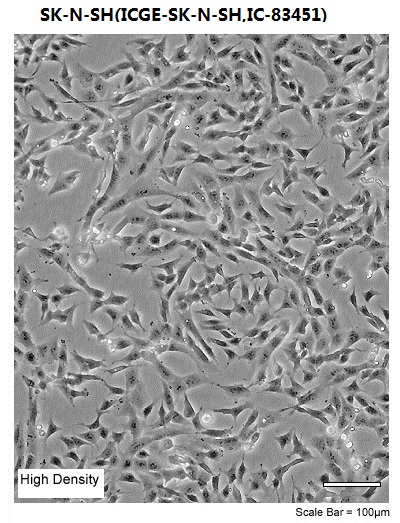

| Morphology | epithelial |

| Culture Properties | adherent |